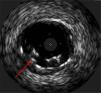

The procedure was performed by radial approach using a 7F guiding catheter. Plaque preparation was performed with rotational atherectomy using a 1.5 mm burr (Figure 3) and further predilation with a cutting balloon (3-3.5 mm). After balloon dilatation, rupture of severely calcified plaque was detected by IVUS (Eagle Eye; Volcano Corporation, Rancho Cordova, CA, USA), so we proceeded to implant a 3.5 mm×20 mm CRE 8 DES in the LM and LAD (Figures 4 and 5). At this point the wire was accidentally pulled back and was reintroduced into the LM and LAD. Post-dilatation was performed with a 4 mm non-compliant balloon. IVUS examination with manual pull-back at this stage revealed that the proximal part of the stent in the LM had been crushed as a result of lateral reintroduction of the wire through a proximal stent strut. The patient remained stable with normal flow in the LM and LAD. Guided by IVUS, a second wire (Sion, Asahi Intecc, Japan), with a 30° bend in its 1 mm distal tip, was introduced within the crushed stent segment (Figure 6). Once the guidewire was positioned inside the stent, progressive dilations with small (1.5 mm) to large (4 mm) balloons were performed until the stent regained its cylindrical shape (Figure 7). IVUS exploration detected an image suggesting dissection in the proximal end of the stent (Figure 8), and so a second DES (4 mm×8 mm Onyx) was implanted in the ostial-proximal segment of the LM, overlapping the previous stent (Figure 9), with an adequate angiographic final result (Figures 10 and 11). IVUS revealed correct stent expansion and apposition in the LM (Figure 12).

The case presented here is a rare complication produced by accidental wire withdrawal during a LM-PCI. The wire was reintroduced proximally and laterally through a proximal stent strut and subsequent dilatation with a 4 mm non-compliant balloon caused stent crushing in its proximal segment. This event was partly due to an underexpanded stent segment in the LM related to the size of the stent (3.5 mm). IVUS was crucial in this case to identify the problem despite an almost normal angiographic image, and it enabled the introduction of a wire into the correct lumen and the reconstruction of the crushed segment after multiple balloon dilatations. Another useful technique to detect lateral stent compression would have been stent boost imaging, but this was not available in our catheterization laboratory at the time the procedure was performed.